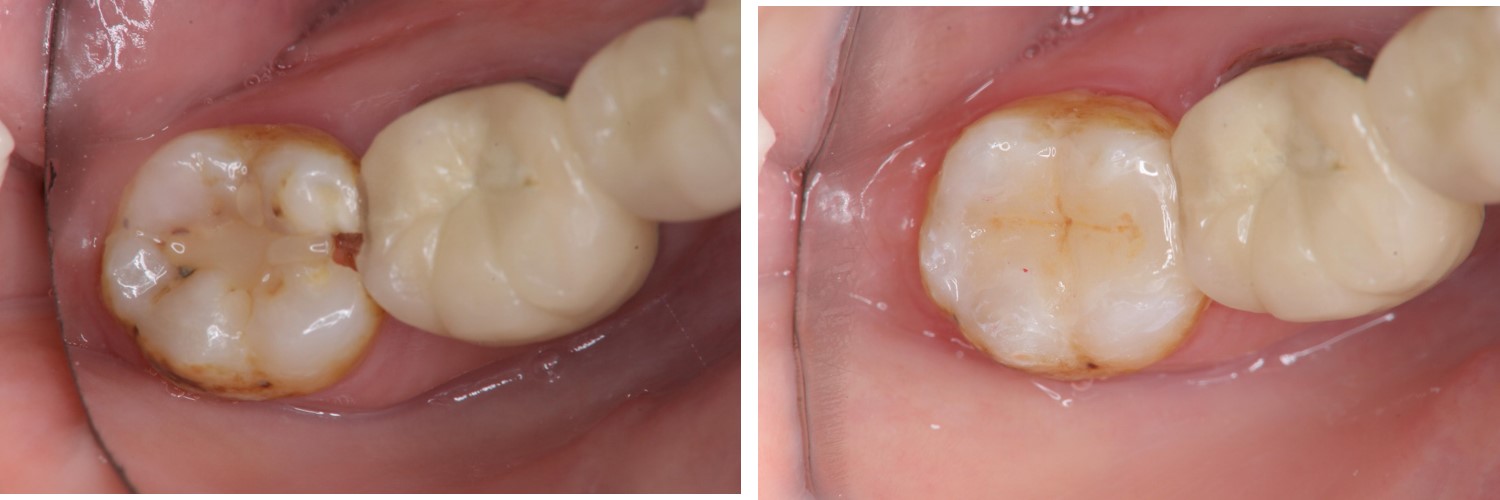

治療前,右下顎第二大臼齒二次蛀牙

右下顎第二大臼齒二次蛀牙

術前、術後比較